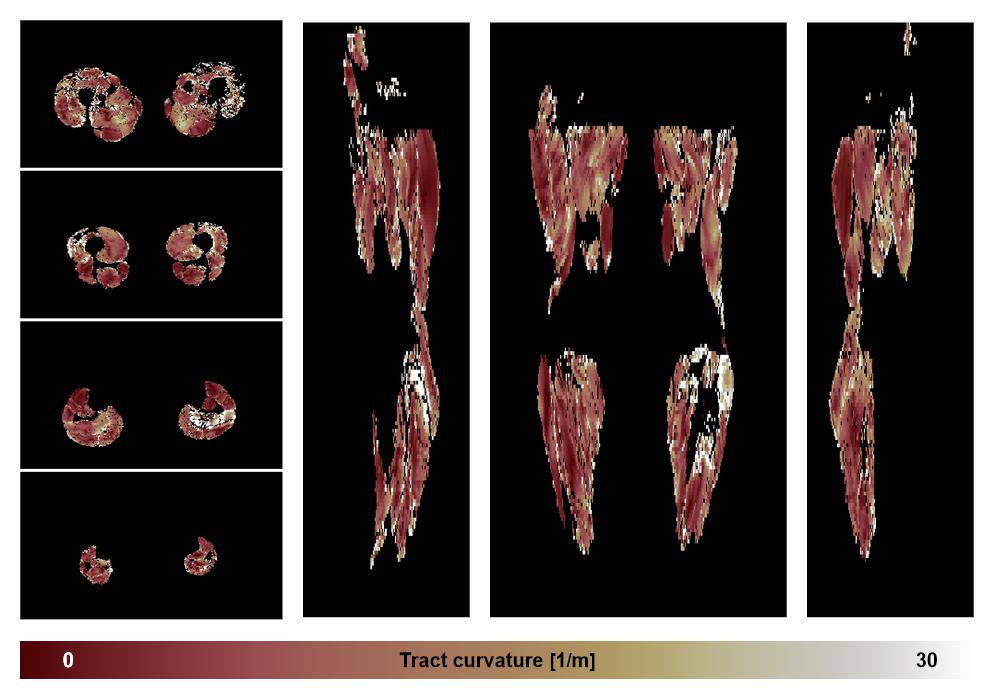

• Muscle fiber curvature map

Muscle fiber tract curvature map based on whole leg DTI based fiber tractography.